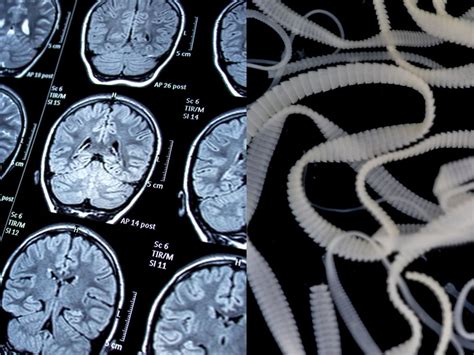

Pics Of A Tapeworm: Educational Value

Visual aids, such as pics of a tapeworm, are invaluable for educational purposes. They provide a clear and detailed view of the parasite's structure, life cycle, and behavior. These images can be used in classrooms, medical training programs, and public health campaigns to raise awareness about tapeworm infections and their prevention.

For example, images of tapeworm eggs, larvae, and adult worms can help students and healthcare professionals understand the different stages of the parasite's life cycle. Pictures of infected tissues or organs can illustrate the damage caused by tapeworm infections, emphasizing the importance of prevention and treatment.

Adult Worms Identifying the structure and behavior of adult tapeworms.

Infected Tissues Illustrating the damage caused by tapeworm infections.